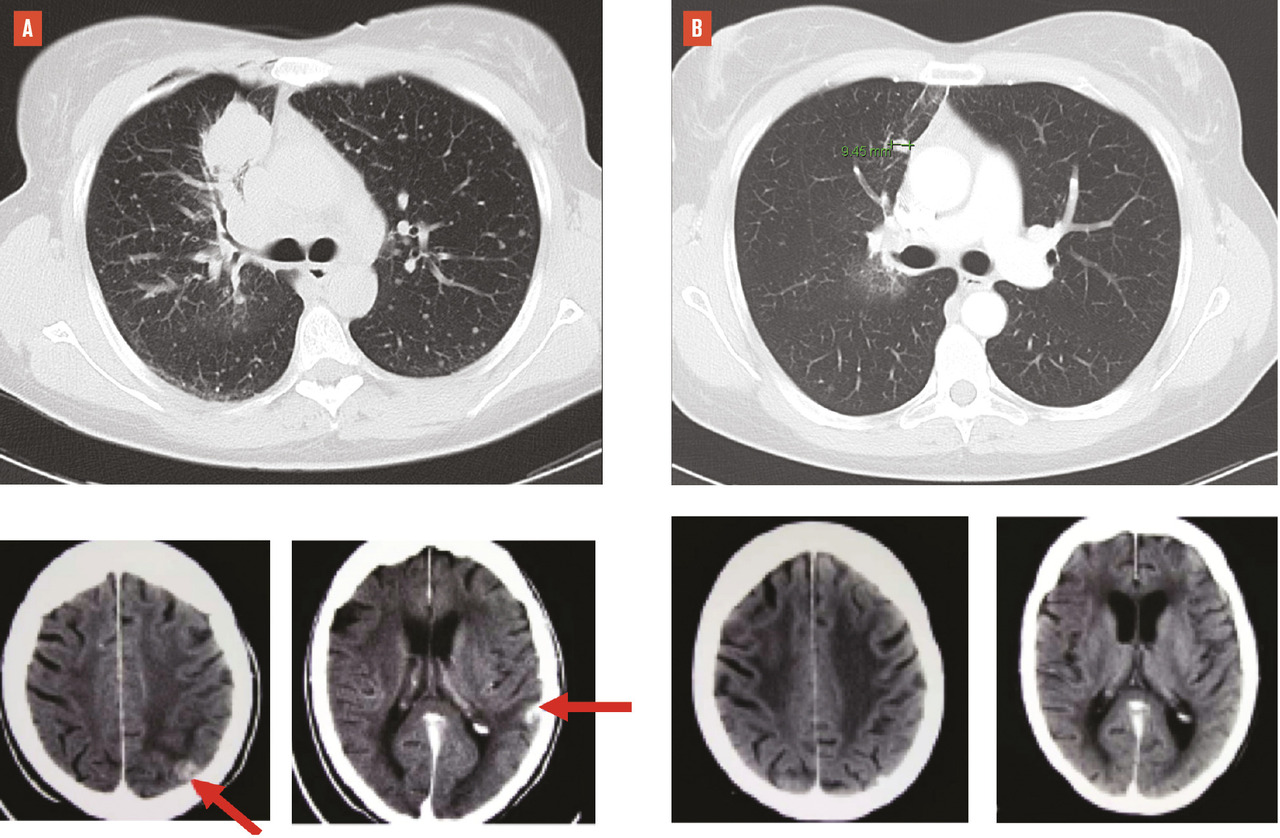

Le diagnostic du cancer pulmonaire, comme le bilan d’extension, a bénéficié de l’essor des scanner hélicoïdaux, dont les progrès techniques ont permis une imagerie toujours plus précise et rapide, avec une irradiation qui n’a cessé de décroître au fil du temps.1 La tomodensitométrie couplée à la tomographie à émission de positons (TEP/TDM), rapidement démocratisée dans la décennie 2000-2010, a permis un bilan d’extension plus exhaustif, complété par l’imagerie par résonance magnétique (IRM) cérébrale, bien que son exactitude n’atteigne pas 100 %, avec des faux négatifs notamment liés à la taille infracentimétrique de certaines lésions. Les faux positifs justifient une vérification histologique systématique des images ganglionnaires médiastinales, qui a bénéficié de l’essor et de la diffusion, dans les services de pneumologie, de l’écho-endoscopie bronchique avec une exploration exhaustive du médiastin et un diagnostic histologique précis de l’extension ganglionnaire des cancers bronchopulmonaires.

La critique avancée contre les tenants d’une amélioration du pronostic est donc le biais de meilleure classification de l’extension tumorale, du fait de l’amélioration de ces techniques diagnostiques, ou effet « Will Rogers ». En effet, le bilan d’extension étant plus fiable, les stades précoces de 2020 sont plus sûrement des stades précoces de bon pronostic qu’ils ne l’étaient il y a 20 ans, avec des techniques d’explorations moins précises. De même, les stades métastatiques se sont enrichis de patients avec faible diffusion métastatique (les stades IVa ou IVb de l’actuelle classification), extension qui n’aurait pas été détectée comme telle il y a 20 ans, et ces patients vivent donc plus longtemps que ceux avec une forte masse tumorale métastatique (les IVc), que ne ratait pas le bilan d’extension, même moins précis, d’il y a 20 ans. Cet effet de migration des stades est certain mais, pour autant, nous tenterons de montrer que la survie des patients s’est réellement améliorée, au-delà de ce biais épidémiologique bien connu.